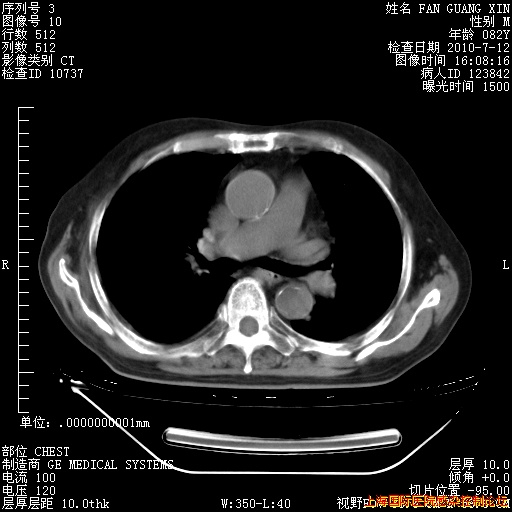

今天CT

整整相隔30天的肺部CT好像有所好转啊。甲强龙减量第3天,需要观察体温。